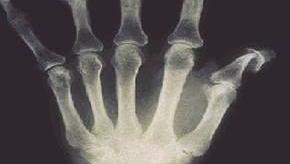

Read ArticleFUTURE 5 - Secukinumab and Less Radiographic Progression in Psoriatic Arthritis

The FUTURE 5 trial studied the effect of secukinumab (SEC) on radiographic progression through 52 weeks in patients with active psoriatic arthritis (PsA) and found that SEC was clinically and radiographically superior to placebo (PBO).

Patients received s.c. secukinumab 300 mg load (300 mg), 150 mg load (150 mg), 150 mg no load regimens or placebo at baseline, at weeks 1, 2 and 3 and every 4 weeks starting at week 4. The majority (87%) of patients enrolled at baseline remained in the study for 52 weeks.